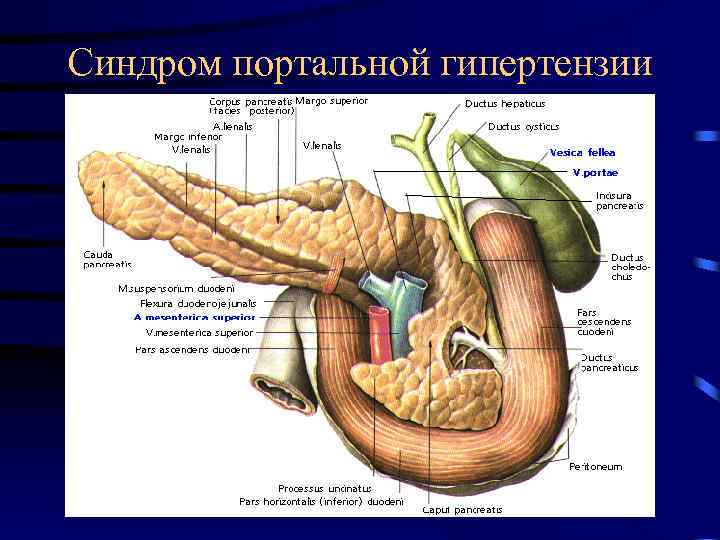

Синдром портальной гипертензии